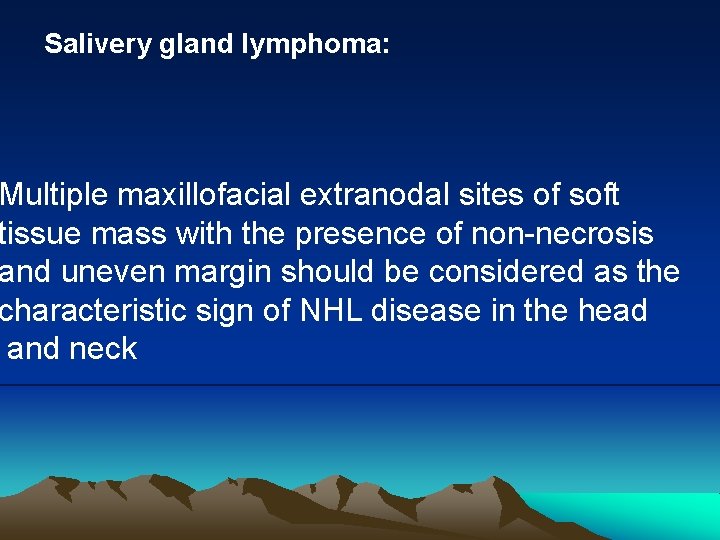

Salivery gland lymphoma: Multiple maxillofacial extranodal sites of soft tissue mass with the presence of non-necrosis and uneven margin should be considered as the characteristic sign of NHL disease in the head and neck